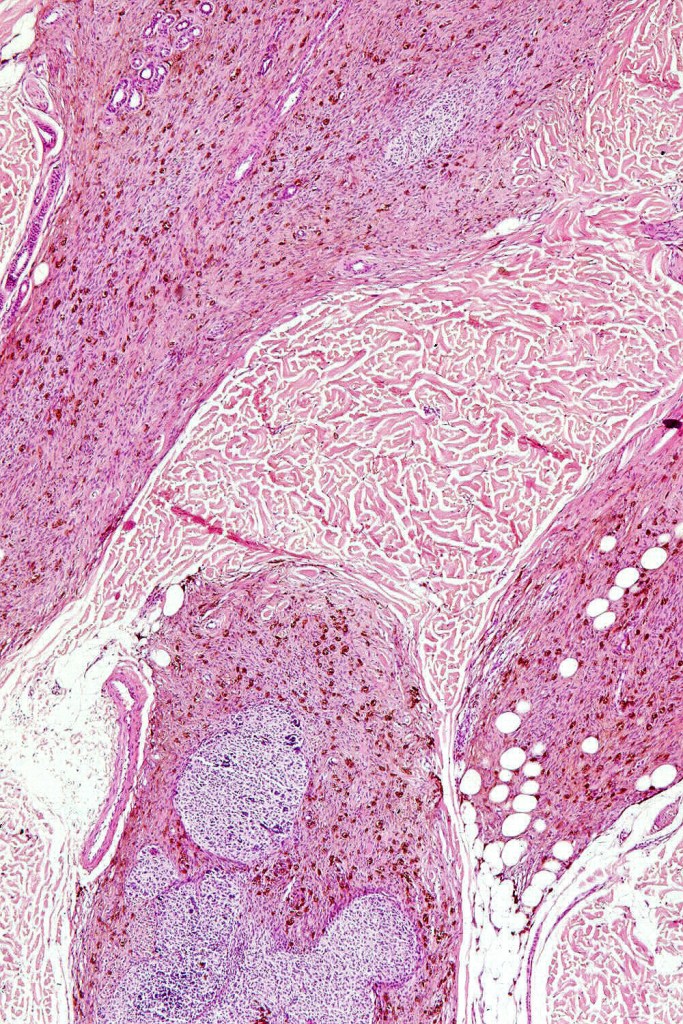

•Most characteristic is the dumbbell silhouette although a plague morphology may also be encountered

•Combined nevus variant

•Admixture of spindle cells, pigmented bipolar or dendritic cells & melanophages

•Stromal fibrosis, myxoid change, vascular hyalinization with cyst formation are often seen

•Some tumors are composed spindle cells in a fascicular or neuronevoid pattern

•Perineural involvement may be seen